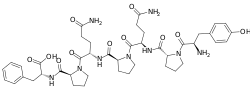

Opioid peptides

Endomorphins

Endorphins

Structures

Enkephalins

Structures

| Enkephalins | ||||

|---|---|---|---|---|

DAMGO DAMGO |

||||

Propeptides

Others / unknown

- Adrenorphin

- Amidorphin

- Biphalin

- Casokefamide

- Casomorphins

- Cytochrophin-4

- DALDA (Tyr-D-Arg-Phe-Lys-NH2)

- Deltorphin I

- Deltorphin II

- Deprolorphin

- Dermorphin

- DPDPE

- Frakefamide

- Gliadorphin

- Gluten exorphins

- Hemorphin-4

- Metkefamide

- Morphiceptin

- Nociceptin

- Octreotide

- Opiorphin

- Rubiscolin

- Soymorphins

- Spinorphin

- TRIMU 5

- Tynorphin

- Valorphin

- Zyklophin

Structures

| Other or unknown opioid peptides | ||||

|---|---|---|---|---|

Adrenorphin Adrenorphin |

Amidorphin Amidorphin |

Casomorphin Casomorphin |

DALDA DALDA |

|

DPDPE DPDPE |

Endomorphin-1 Endomorphin-1 Endomorphin-2 Endomorphin-2 |

Gliadorphin Gliadorphin |

Morphiceptin Morphiceptin | |

Nociceptin Nociceptin |

Octreotide Octreotide |

Opiorphin Opiorphin |

Rubiscolin Rubiscolin |

TRIMU 5 TRIMU 5 |